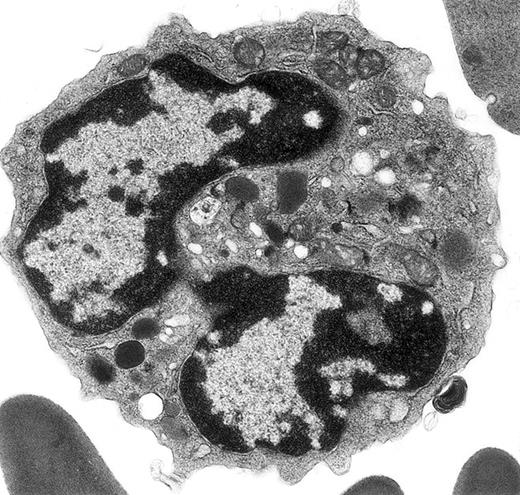

Electron micrograph shows a mature mouse basophil that was present in the FcεR+ cells sorted from normal mouse bone marrow.

(For more details, see Seder et al3and Dvorak et al.4) The mature nucleus has heavily condensed chromatin in 2 lobes. Small numbers of mature electron-dense granules are evident in the cytoplasm. Numerous mitochondria and electron-lucent secretory vesicles constitute the other cytoplasmic organelles in this view. Original magnification, × 23 000.